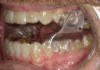

Fig 8. The appliance worn during treatment, anterior view (Fig 8), right side view (Fig 9), left side view (Fig 10), and upper arch view (Fig 11).

Figure 8

Fig 9. The appliance worn during treatment, anterior view (Fig 8), right side view (Fig 9), left side view (Fig 10), and upper arch view (Fig 11).

Figure 9

Fig 10. The appliance worn during treatment, anterior view (Fig 8), right side view (Fig 9), left side view (Fig 10), and upper arch view (Fig 11).

Figure 10

Intraoral scans were taken to document the patient's entire palate and bite registration. Scans were sent to the clinical team for the fabrication of a clear aligner/sleep appliance for the patient to wear; the chosen appliance fits over clear aligners, regardless of the tray number the patient may need (Figure 7 through Figure 11).

After the appliance was delivered, additional photographs were taken with the camera to ensure that the appliance was delivered as intended, to document the case, and to show the patient the ideal fit of the appliance in his mouth as instructions were reviewed with him.